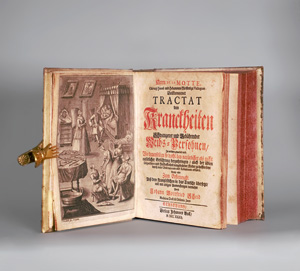

La Motte, Guillaume Mauquest de

Vollkommener Tractat von Kranckheiten schwangerer und gebährender Weibs-Persohnen

Zuschlag

160€ (US$ 182)